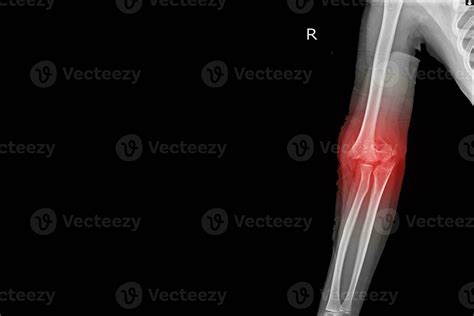

Elbow Joint Effusion occurs when there is an abnormal accumulation of fluid within the joint capsule. The elbow joint is lined with a thin membrane called the synovium, which produces a small amount of fluid to lubricate the cartilage and allow for smooth movement. When the joint is irritated—due to trauma, infection, or chronic inflammatory diseases—the synovium overproduces this fluid, leading to swelling, stiffness, and restricted range of motion.

Because the elbow joint capsule is relatively tight, even a small increase in fluid volume can cause significant pressure. This pressure is often what leads to the sharp pain or aching sensation patients report. It is important to distinguish effusion from bursitis, as the former occurs inside the joint space, whereas bursitis typically occurs in the bursa sac outside the joint.

• Warmth and Redness: If the area feels hot to the touch, it may indicate an underlying infection or acute inflammation.

• elbow joint effusion x ray